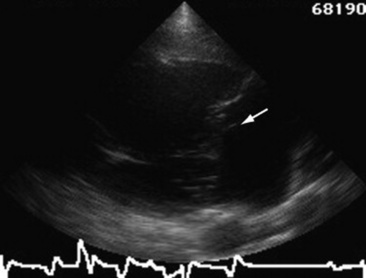

Diagnosis of valvular disease is best performed with a complete echocardiographic examination including M-mode, two-dimensional, and Doppler echocardiography. Two-dimensional echocardiography is superior to M-mode for detection of valvular abnormalities (Figs. 30-8 and 30-9), measurement of valvular masses (Fig. 30-9, B), and the global assessment of ventricular function, but chamber enlargement, high-frequency vibrations of the valve leaflets, and shortening fraction (an indication of ventricular systolic function) can be determined by both. Pulsed wave, continuous wave, and color flow Doppler echocardiography can be used to semiquantitate the severity of valvular regurgitation.92-97 The size of the regurgitant jet detected with pulsed wave or color flow echocardiography is one indicator of the severity of the valvular insufficiency.98 The duration of the mitral regurgitation jet is also important in assessing severity. Clinically insignificant jets of regurgitation are detected only just behind the valve when it is closed. Valvular insufficiency is mild when the jet occupies one third or less of the receiving chamber, moderate when the jet occupies greater than one third but less than two thirds of the receiving chamber, and severe when the jet occupies greater than two thirds of the receiving chamber.

image image

Fig. 30-9 Echocardiograms of a bacterial endocarditis lesion on the aortic valve of a horse. The lesion can be seen on the aortic valve M-mode (A) as a thick echoic band (arrow) and is measured in the two-dimensional echocardiographic image of the left parasternal long axis view (B).